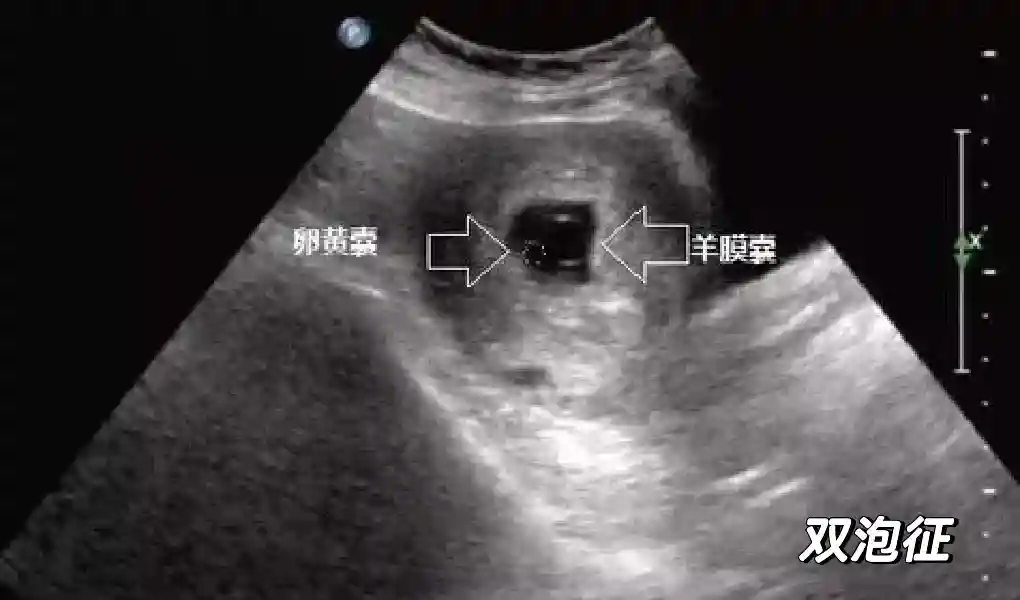

5??羊膜:早孕期羊膜囊菲薄,超声常不能显示。孕7周以后加大增益或者用高频超声可以显示羊膜。羊膜囊位于绒毛膜内,胚胎位于羊膜囊内。随着胚胎增长,羊水增多,羊膜囊增大,孕12-16周时,羊膜与绒毛膜全部融合,胚外体腔消失。宫腔线一侧内膜内一圆形增强回声区,中央有小囊状液性暗区,宫腔线局部突起变形,称蜕膜内征,用于判断早早孕。

1??妊娠囊:早期妊娠囊:正常妊娠囊位于宫腔上段,表现为宫腔内圆形或椭圆形的无回声区,周边为完整的、厚度均匀的强回声环,强回声环厚度≥2mm,强回声是妊娠绒毛的回声,随着妊娠囊的增大,形成特征性的“双环征” ,10周以后消失。正常的妊娠囊增长速度是平均 1 mm /d。